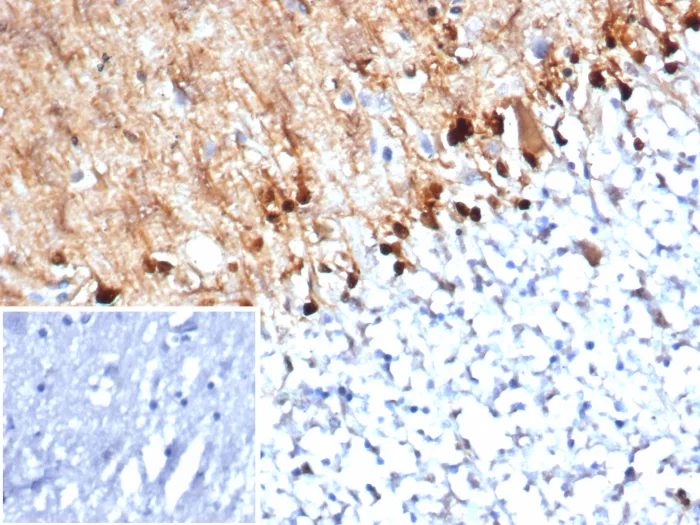

Formalin-fixed, paraffin-embedded human brain stained with S100B Mouse Monoclonal Antibody (S100B/4152) at 2ug/ml. Inset: PBS instead of primary antibody, secondary negative control.